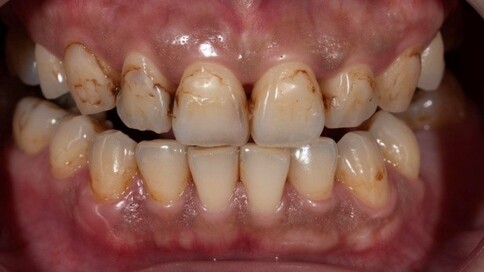

✨ 四、 陶瓷貼片:美學微整

Case 9:氧化鋯貼片改善四環黴素變色。

Case 10:改善不均勻齒色,修復磨耗邊緣。